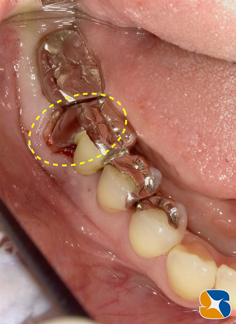

後日ブリッジを外してみると、ブリッジの土台の歯根が見事に粉々に砕けていました。